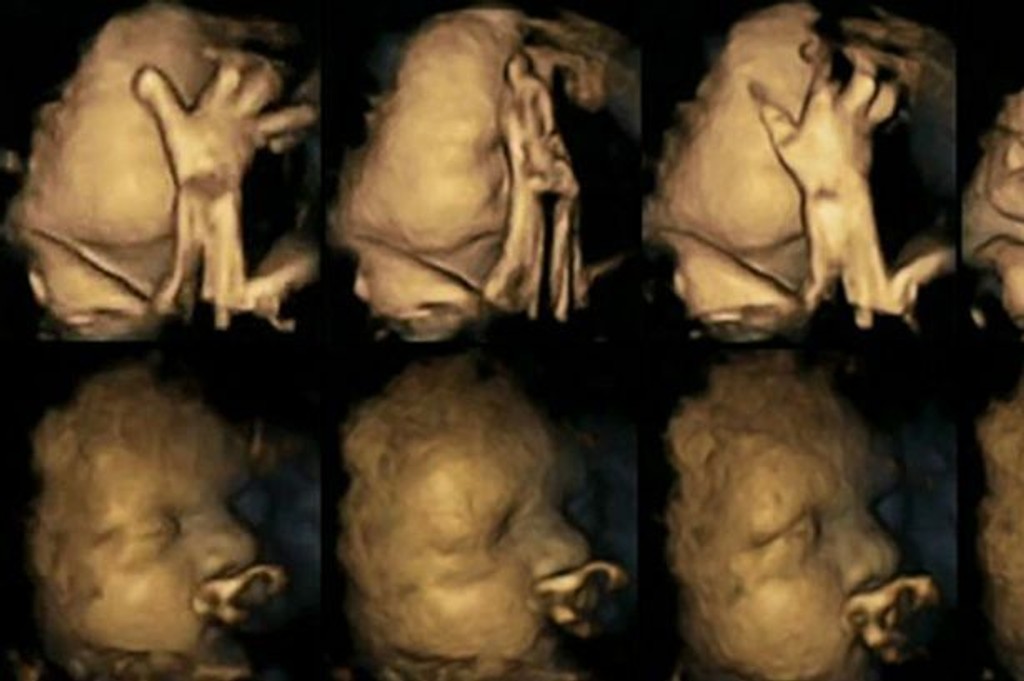

Ultrazvukové snímky ukazujú, aký vplyv má fajčenie na bábätko

Toto by malo ľahšie prinútiť tehotné fajčiarky odhodiť cigarety, ktoré zvyšujú riziko predčasného pôrodu, dýchacie ťažkosti a syndróm náhleho úmrtia bábätka.

Ultrazvukové 4D vyšetrenie je momentálne veľmi populárne. Rodičia tak môžu vidieť, ako ich bábätko vyzerá a ešte počas jeho pobytu v brušku môžu hádať, na koho sa viac podobá. Ale vedci sa ho rozhodli využiť aj na niečo iné. Doktorka Nadja Reissland preskúmala tieto snímky a zaznamenala tisícky drobných mimických pohybov v maternici. Pozrela sa aj na to, ako dieťatko reaguje na to, že jeho mama fajčí. Myslia si, že toto ľahšie prinúti tehotné fajčiarky odhodiť cigarety, ktoré zvyšujú riziko predčasného pôrodu, dýchacie ťažkosti a syndróm náhleho úmrtia bábätka.

Monitorovala 20 budúcich mamičiek v nemocnici Jamesa Cooka v Middlesbourghu. Z toho štyri tehuľky vyfajčili 14 cigariet denne. Študovala ich ultrazvukové snímky z 24., 28., 32. a 36. týždňa. Ich bábätká sa výrazne rýchlejšie pohybovali a stále si chytali tváričku či hlavu, čo bábätká nefajčiarok nerobia v takej miere. Čím viac sa blíži dátum ich príchodu na svet, tým menej to robia, píše mirror.co.uk.

Doktorka Reissland tvrdí, že deti fajčiarok môžu mať pomalší vývoj centrálneho nervového systému. Svojou štúdiou ich nechce démonizovať. Chce vyzvať k väčšej podpore tehotných fajčiarok, aby prestali. V súčasnosti fajčí vo Veľkej Británii 12 percent tehotných žien, až 20 percent v oblastiach Druhamu, Darlingtonu a Teesu.

Spoluautor štúdie Brian Francis z univerzity v Lancasteri tvrdí: "Technológia nám umožnila vidieť to, čo bolo donedávna skryté. Odhaľuje, ako fajčenie ovplyvňuje vývoj plodu. Je to ďalší dôkaz negatívnych účinkov fajčenia v tehotenstve."